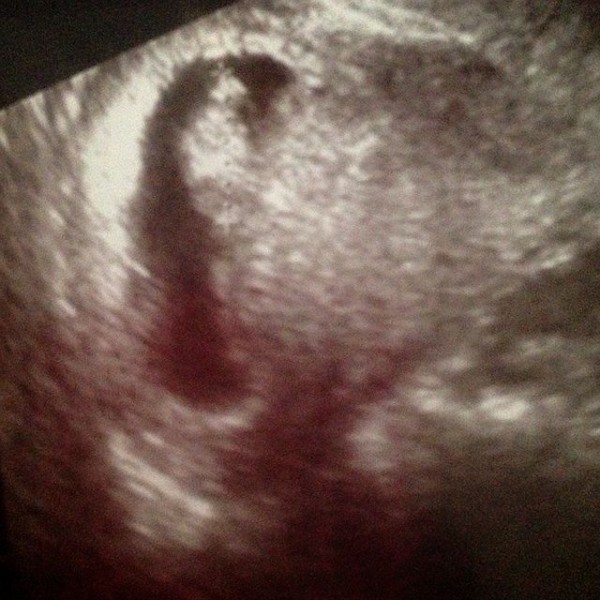

9w 赤ちゃん 驚異の成長 Happy Life